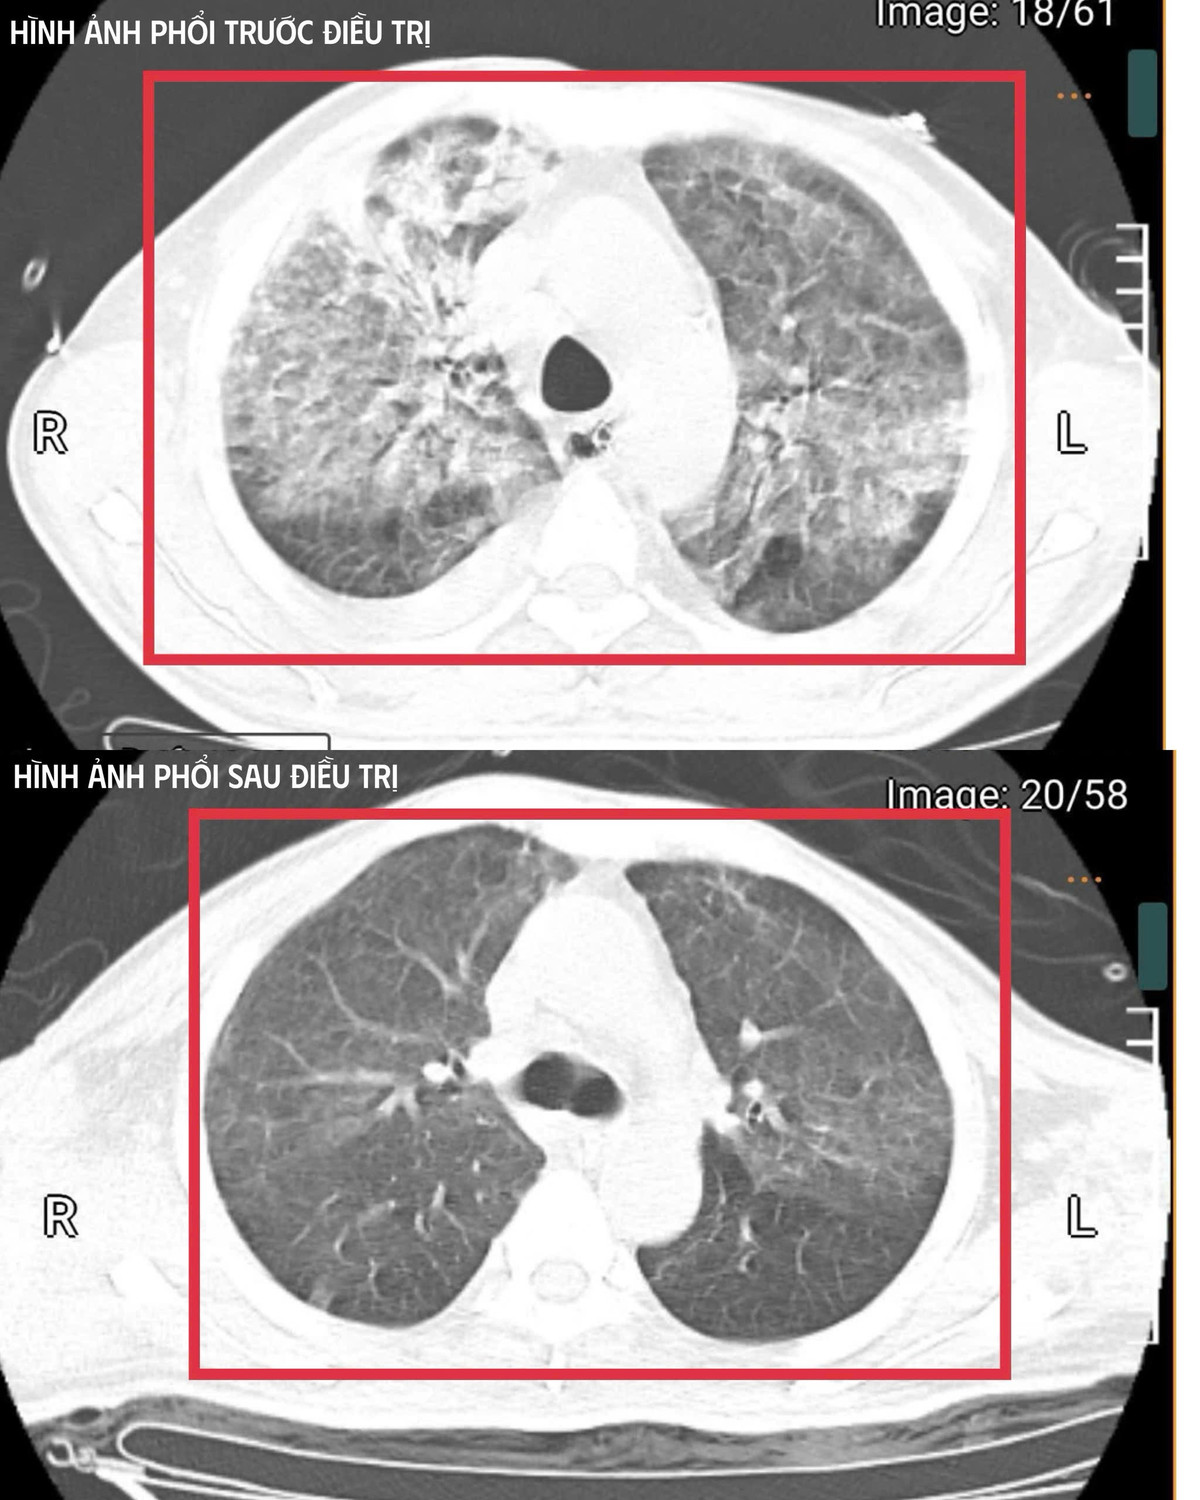

vi-khuan-2.jpg

Hình ảnh tổn thương phổi của bệnh nhân trước và sau điều trị - Ảnh BVCC